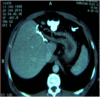

Case reports: We report two cases of huge (25cm and 20cm in diameter, respectively) echinococcal cysts located in the left liver, which presented as a large palpable mass causing compression symptoms. Diagnosis was established with CT scan showing a cystic mass with the characteristic daughter cysts and reactive layer (pericystic wall) consisting of fibrous connective tissue and calcifications. Both patients were treated radically with left hepatectomy and had uneventful postoperative course and no recurrence upon follow-up.